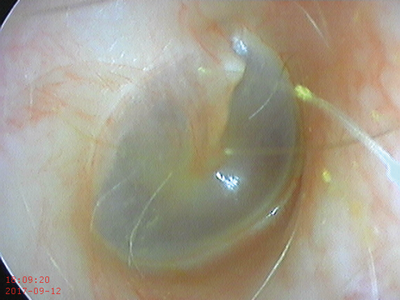

Cupris-TYM - otoscopy image.

Cupris - TYM

Type: Smartphone otoscope adapter for iPhone 5/6 Captures images + videos

Cost: £129

Image quality: 32%

Field of view: 42%

Ease of use: 58%

Comments: The images taken were mostly too dark and lacking in colour (tested with iPhone 6s). The picture was too zoomed in, due to a poor field of view, which made it difficult to navigate the tympanic membrane and get representative images. This product does have the advantage of not requiring any additional equipment, such as endoscopes or light sources, which is useful in low resource settings [1].